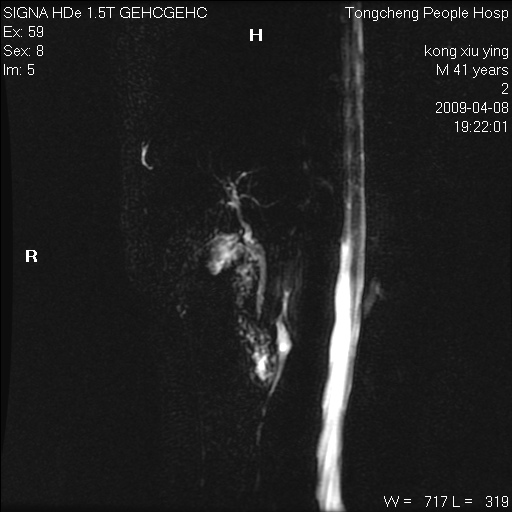

标题: CL1008:【经典】胆囊石榴籽样结石。

女,41岁。健康体检——彩超提示:胆囊显示不清。平素健康,无不适感。

腹部mr扫描及mrcp,图像如下: